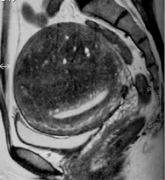

子宫肌瘤治疗前影像学的角色包括: 确定子宫肌瘤的诊断 除外其它病例情况 决定子宫肌瘤的数目,大小和位置 = 子宫肌瘤的图谱以便决定可能的治疗选择。 超声: 超声的优点是便宜和容易应用的影像学方式,也是妇科检查的常规。丰富经验的老手足以决定子宫肌瘤...